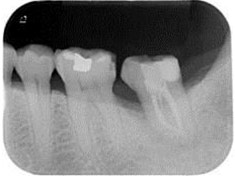

牙周初診時患者之口內觀。口內明顯牙菌斑及牙結石堆積。全口嚴重牙齦紅腫。治療前X光片。#37的近心側有較深的骨內缺損,剩餘齒槽骨高度只有20%。

A圖為#37根管治療完後的三個月放射線攝影根尖片。